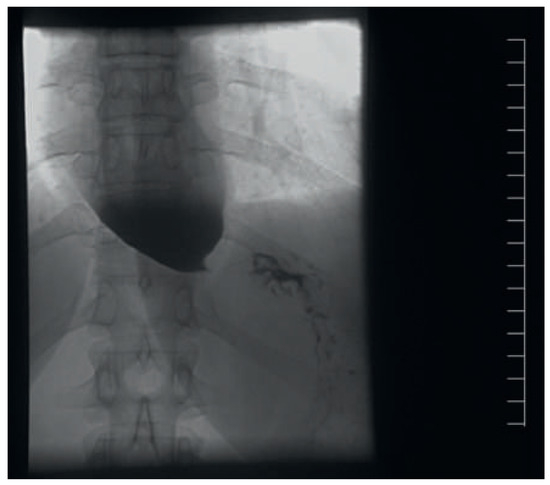

A 41-year-old women with Ebstein’s anomaly required tricuspid valve replacement six years ago. At that time a biological prosthesis was implanted. The tricuspid valve prosthesis became severely stenotic within five years. Instead of re-do surgery, th...